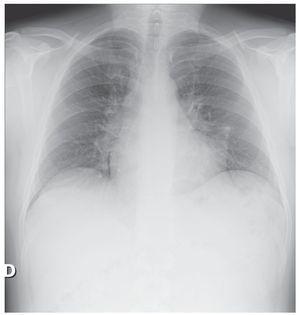

Derrame pleural masivo secundario a pseudoquiste pancreático

Salinas Lasa, Iturbe Susilla, Díaz Urquizo, Ponce Sánchez, Bustamante Madariaga, Crespo Notario

Revista de Patología Respiratoria 2011;14:104-5

Acceso a texto completo